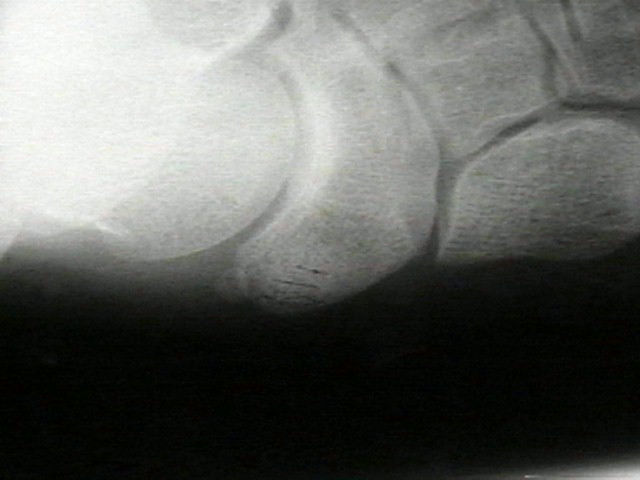

Radiographs

• radiographs may not be helpful if the accessory ossification is not ossified;

• the standard oblique of the foot (medial internal oblique view) will not show the accessory ossicle in profile;

• the lateral (external) oblique view is the radiograph of choice;

• although accessory navicular appears distinct from the navicular on x-rays, it is actually attached by fibrous tissue or cartilage;

Accessory Navicular 2 Accessory Navicular 3 Accessory Navicular 4